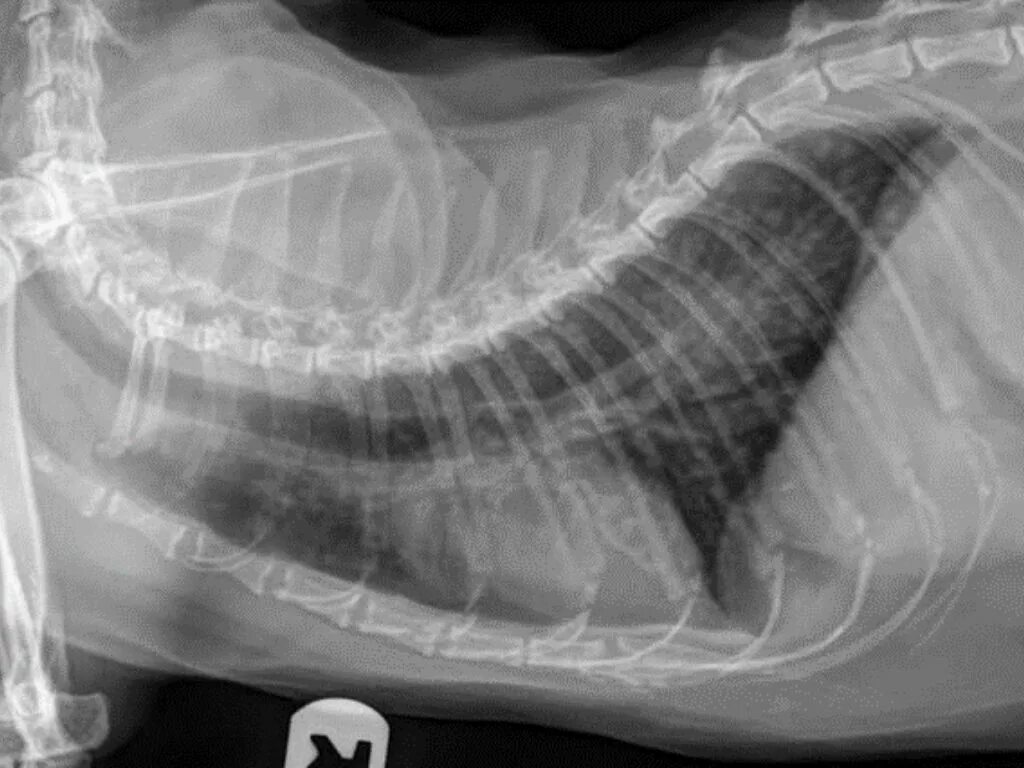

Астма у кота